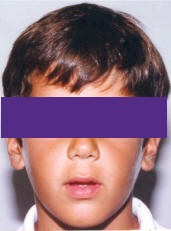

Un niño de 9 años se

presenta a la consulta con maloclusión de clase II Div. 1, en

dentadura mixta, con desviación de línea media hacia el lado

derecho, severa protrusión incisiva, sin erupcionar pieza 12. (Fig.

1, 2)

1) Extraoral.- Un

joven que al examen de frente se nota con proporciones equilibradas,

no obstante en el análisis de pefil se puede advertir un aparente

incremento del tercio inferior de la cara, parecería una leve

dificultad en el cierre labial, la mandíbula se ve levemente

retrognática. (Fig. 1)

Fig. # 1.- Fotografías del

paciente de 9 años de edad en las cuales podemos

observar su rostro de frente y perfil, en las fotos de

perfil podemos advertir un aparente incremento del

tercio inferior de la cara y leve dificultad en el

cierre labial. |

En la fotografía de

frente el niño se ve bien, sin embargo se podría señalar, leve falta

del cierre labial, de perfil se observa un ligero aumento del tercio

inferior de la cara, de igual forma que un retrognatismo leve. (Fig.

1)